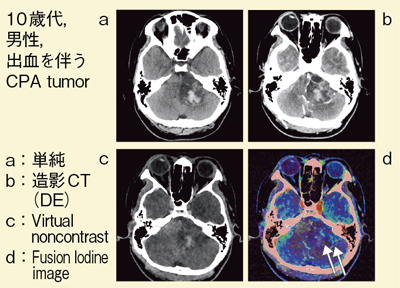

楽天ブックス: エビデンスに基づくCT用造影剤の投与と安全対策 - 粟井 和夫 - 9784758321204 : 本, 頭部:Brain Hemorrhage 渡邉嘉之(大阪大学大学院医学研究科 放射線医学講座)- シーメンス・ジャパン株式会社 - inNavi Suite

頭部:Brain Hemorrhage 渡邉嘉之(大阪大学大学院医学研究科 放射線医学講座)- シーメンス・ジャパン株式会社 - inNavi Suite